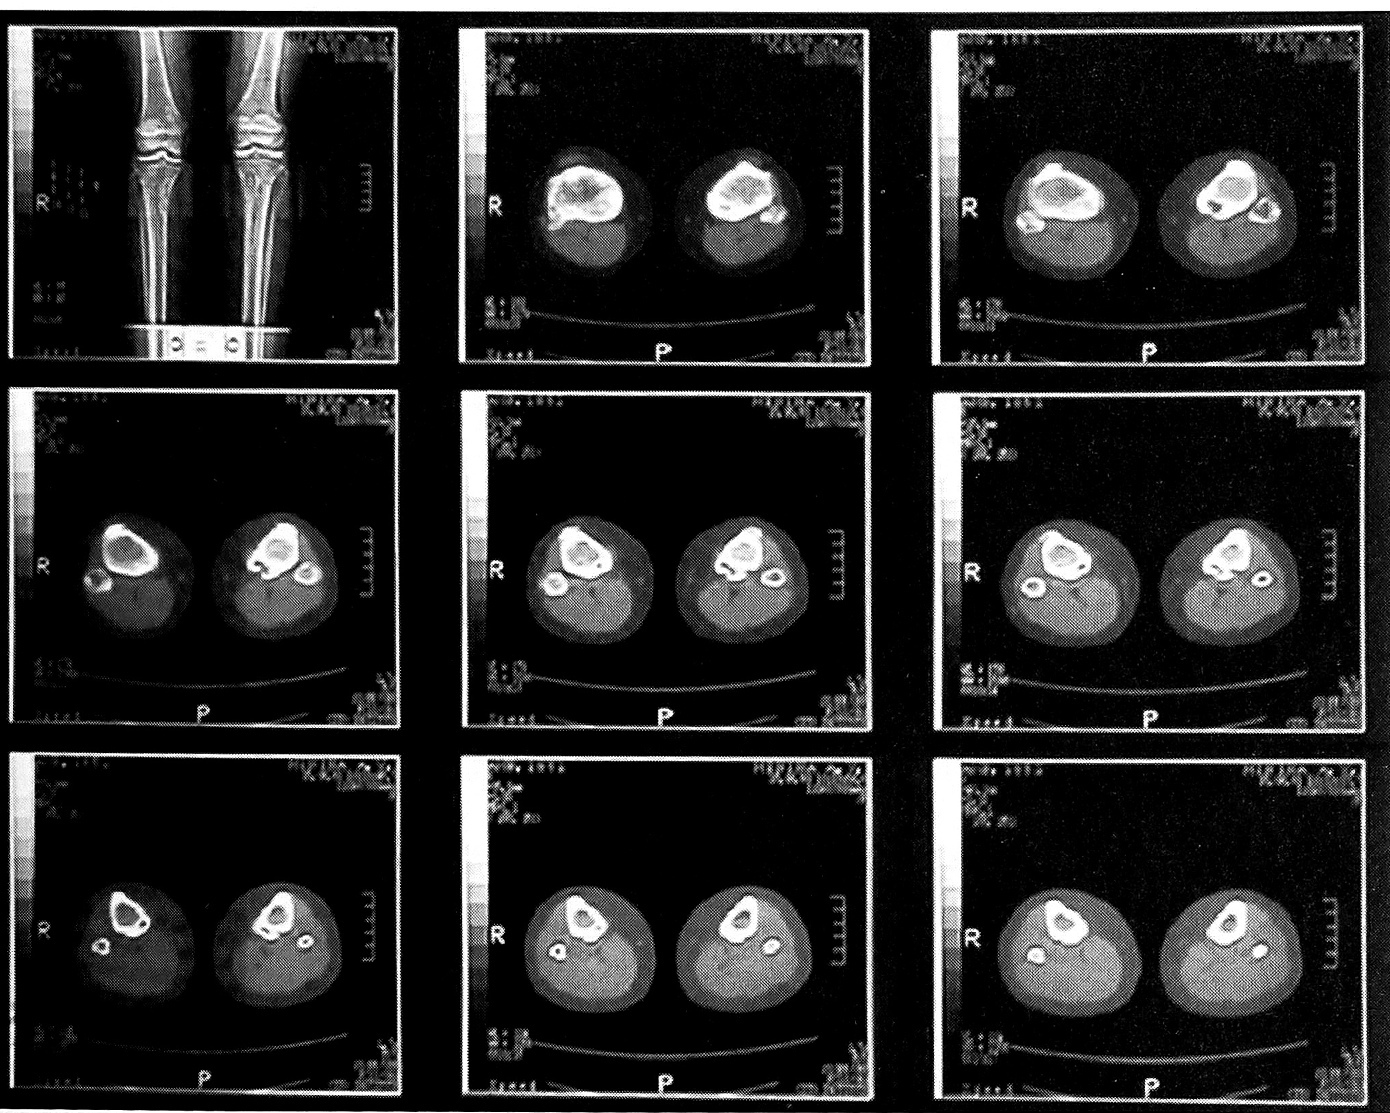

КТ была проведена 2 больным. При анализе томограмм выявлены изменения коркового слоя метафизарных отделов длинных костей в виде краевых и интракортикальных дефектов протяженностью от 25 до 80 мм с четкими склерозированными контурами. Относительная плотность ткани в очагах составляла от 40 до 60 единиц Хаунсфилда. Данный метод позволял установить истинные размеры дефекта и определить объем предстоящего хирургического вмешательства (рис. 3).

Рис. 3. Компьютерная томограмма больной М. с синдромом Jaffe—Campanacci.